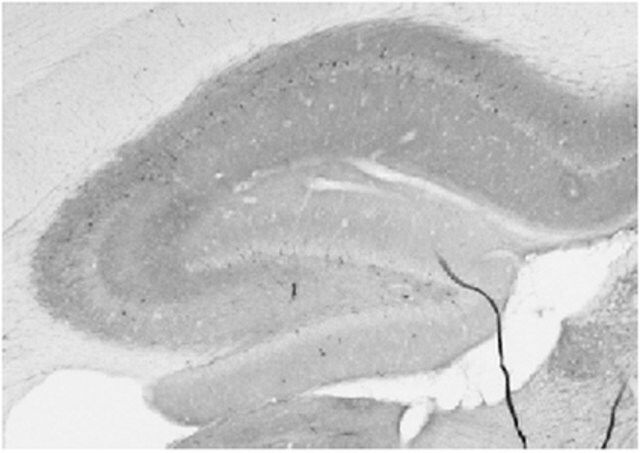

| Application【应用】 | Immunohistochemistry Analysis: A representative lot detected GABA(A)R, Alpha1 Protein in rat hippocampus tissue (Prof. J. Trimmer, University of California, Davis). Western Blot Analysis: A representative lot detected GABA(A)R, Alpha1 Protein in RBM membrane extracts, COS cell lysates transiently transfected with GABA(A)R, Alpha1 Protein, and in WT mice but not in GABA(A)R Alpha1 knockout mice. Research Category Neuroscience This Anti-GABA(A)R, Alpha1 Protein Antibody, clone N95/35 is validated for use in Western Blotting, IHC for the detection of GABA(A)R, Alpha1 Protein, clone N95/35. Research Sub Category Neurotransmitters & Receptors |